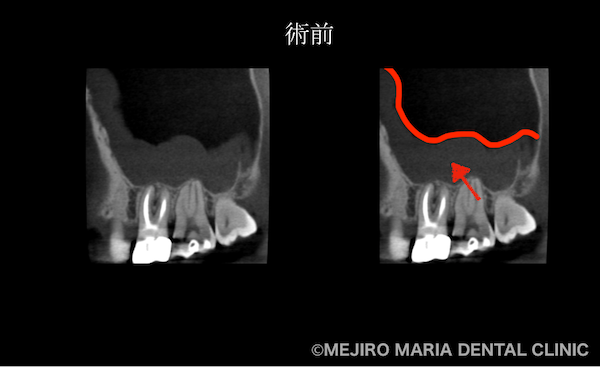

を併発した根尖性歯周炎を、精密根管治療で治癒|術前の歯のCT画像_治療前1.png)

右画像赤矢印部分

患者様によると、1年前に感じた症状は「階段を降りるときに、鋭い歯痛を感じた」とのことで、当時から上顎洞炎(副鼻腔炎)であったことが疑われました。上顎洞炎の場合、時に小臼歯部に、神経を突くような鋭い痛みを覚えることがあります。また、頭痛や頭部を下げるような動作に対する眼下の違和感などが主な症状です。

患者様ご自身は、1年前に根管治療を行った右上4番の歯の予後不良を疑っていました。しかし当院の診査にて、患者様の訴える症状の原因は、数年前に根管治療を行った右上6番の歯の予後不良による根尖性歯周炎と診断しました。